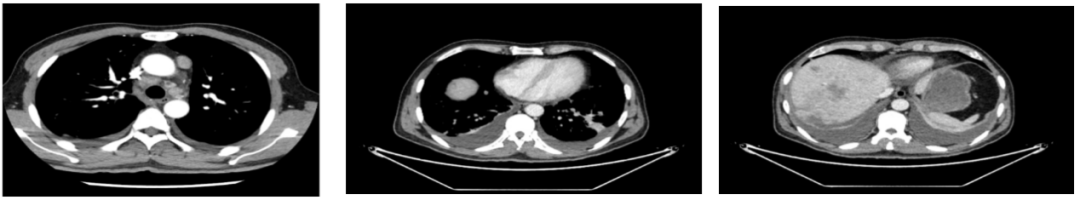

外院CT检查提示:1、两肺多发斑片状、结节影,性质待定,转移瘤?2、纵隔内多发肿大淋巴结;3、肝实质多发稍低密度影,性质待定(转移瘤可能性大)

2018-03-08 PET/CT示:胃癌(?)并全身多发淋巴结转移、肝脏多发转移、双肺上叶多发转移;

△2018-3-19基线CT